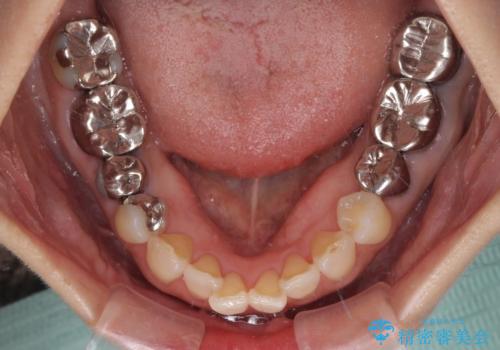

- 近医にて奥歯の抜歯が必要と言われたとのことで来院された患者様です。

診断の結果、奥歯は歯根が破折しており、抜歯が必要な状況でした。

インプラントあるいはブリッジによる補綴治療が考えられましたが、前後の歯が大きな銀歯であったため、オールセラミックブリッジにより3本の歯を審美的に仕上げることとしました。

ブリッジの支台歯は2本とも神経を取り除いている歯であるため、咬合力の強い方ですと、支台歯も歯根破折をするリスクがあります。

今回はそれほど咬合力が強いとは思われなかったため、ブリッジによる補綴治療を行いましたが、念のため、就寝時にはナイトガードとしてマウスピースを装着するようお願いしました。